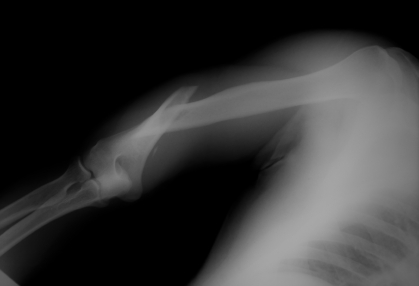

Teenage athletes aren't just making goals and running across the field - a lot of them are getting X-rays each year. Hi, I'm Dr. Cindy Haines, host of HealthDay TV.

More than 7.5 million high-schoolers played sports in a recent year. A new study in the Clinical Journal of Sports Medicine took a closer look at the numbers of broken bones among these young athletes. They used injury reports from 100 American high schools for the 2005 to 2009 academic years.

Fractures made up about 10 percent of all the injuries that occurred in the high-school athletes. The highest rate of fractures happened while playing football, and the lowest was with volleyball. Boys were far more likely to have a broken bone, with 83 percent of fractures occurring in the guys.

Overall, fractures were more than three times as likely to occur during games than practices. The most commonly fractured body parts were the hands or fingers, which accounted for about 28 percent of these injuries. Wrists followed with about 10 percent, then lower legs with about 9 percent.